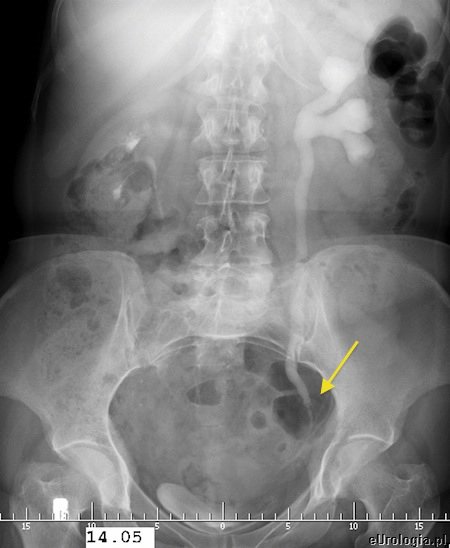

Fot. Cień uwapnionego złogu w rzucie lewego moczowodu na zdjęciu przeglądowym nerek i pęcherza.

Kamica moczowodowa czyli potocznie kamień w moczowodzie jest najczęstszą przyczyną kolki nerkowej. Złogi - kamienie z nerki mogą przemieścić się do moczowodu blokując odpływ moczu z nerki. Zastój moczu w układzie kielichowo - miedniczkowym powoduje napięcie torebki nerkowej i wystąpienie ataku kolki. W zależności od lokalizacji kamień w moczowodzie może być uwidoczniony róznymi sposobami. Kamienie w górnym odcinku moczowodu i w okolicy ujścia pęcherzowego moczowodu czasami możliwe są do uwidocznienia w USG. Większość kamieni w moczowodzie widoczna jest na zdjęciu przeglądowym jamy brzusznej. W celu uwidocznienia miejsca przeszkody w odpływie moczu z nerki wykonywane jest badanie urograficzne. Urografia jest badaniem obrazowym pozwalającym na ocenę czynnościową i anatomiczną układu moczowego.